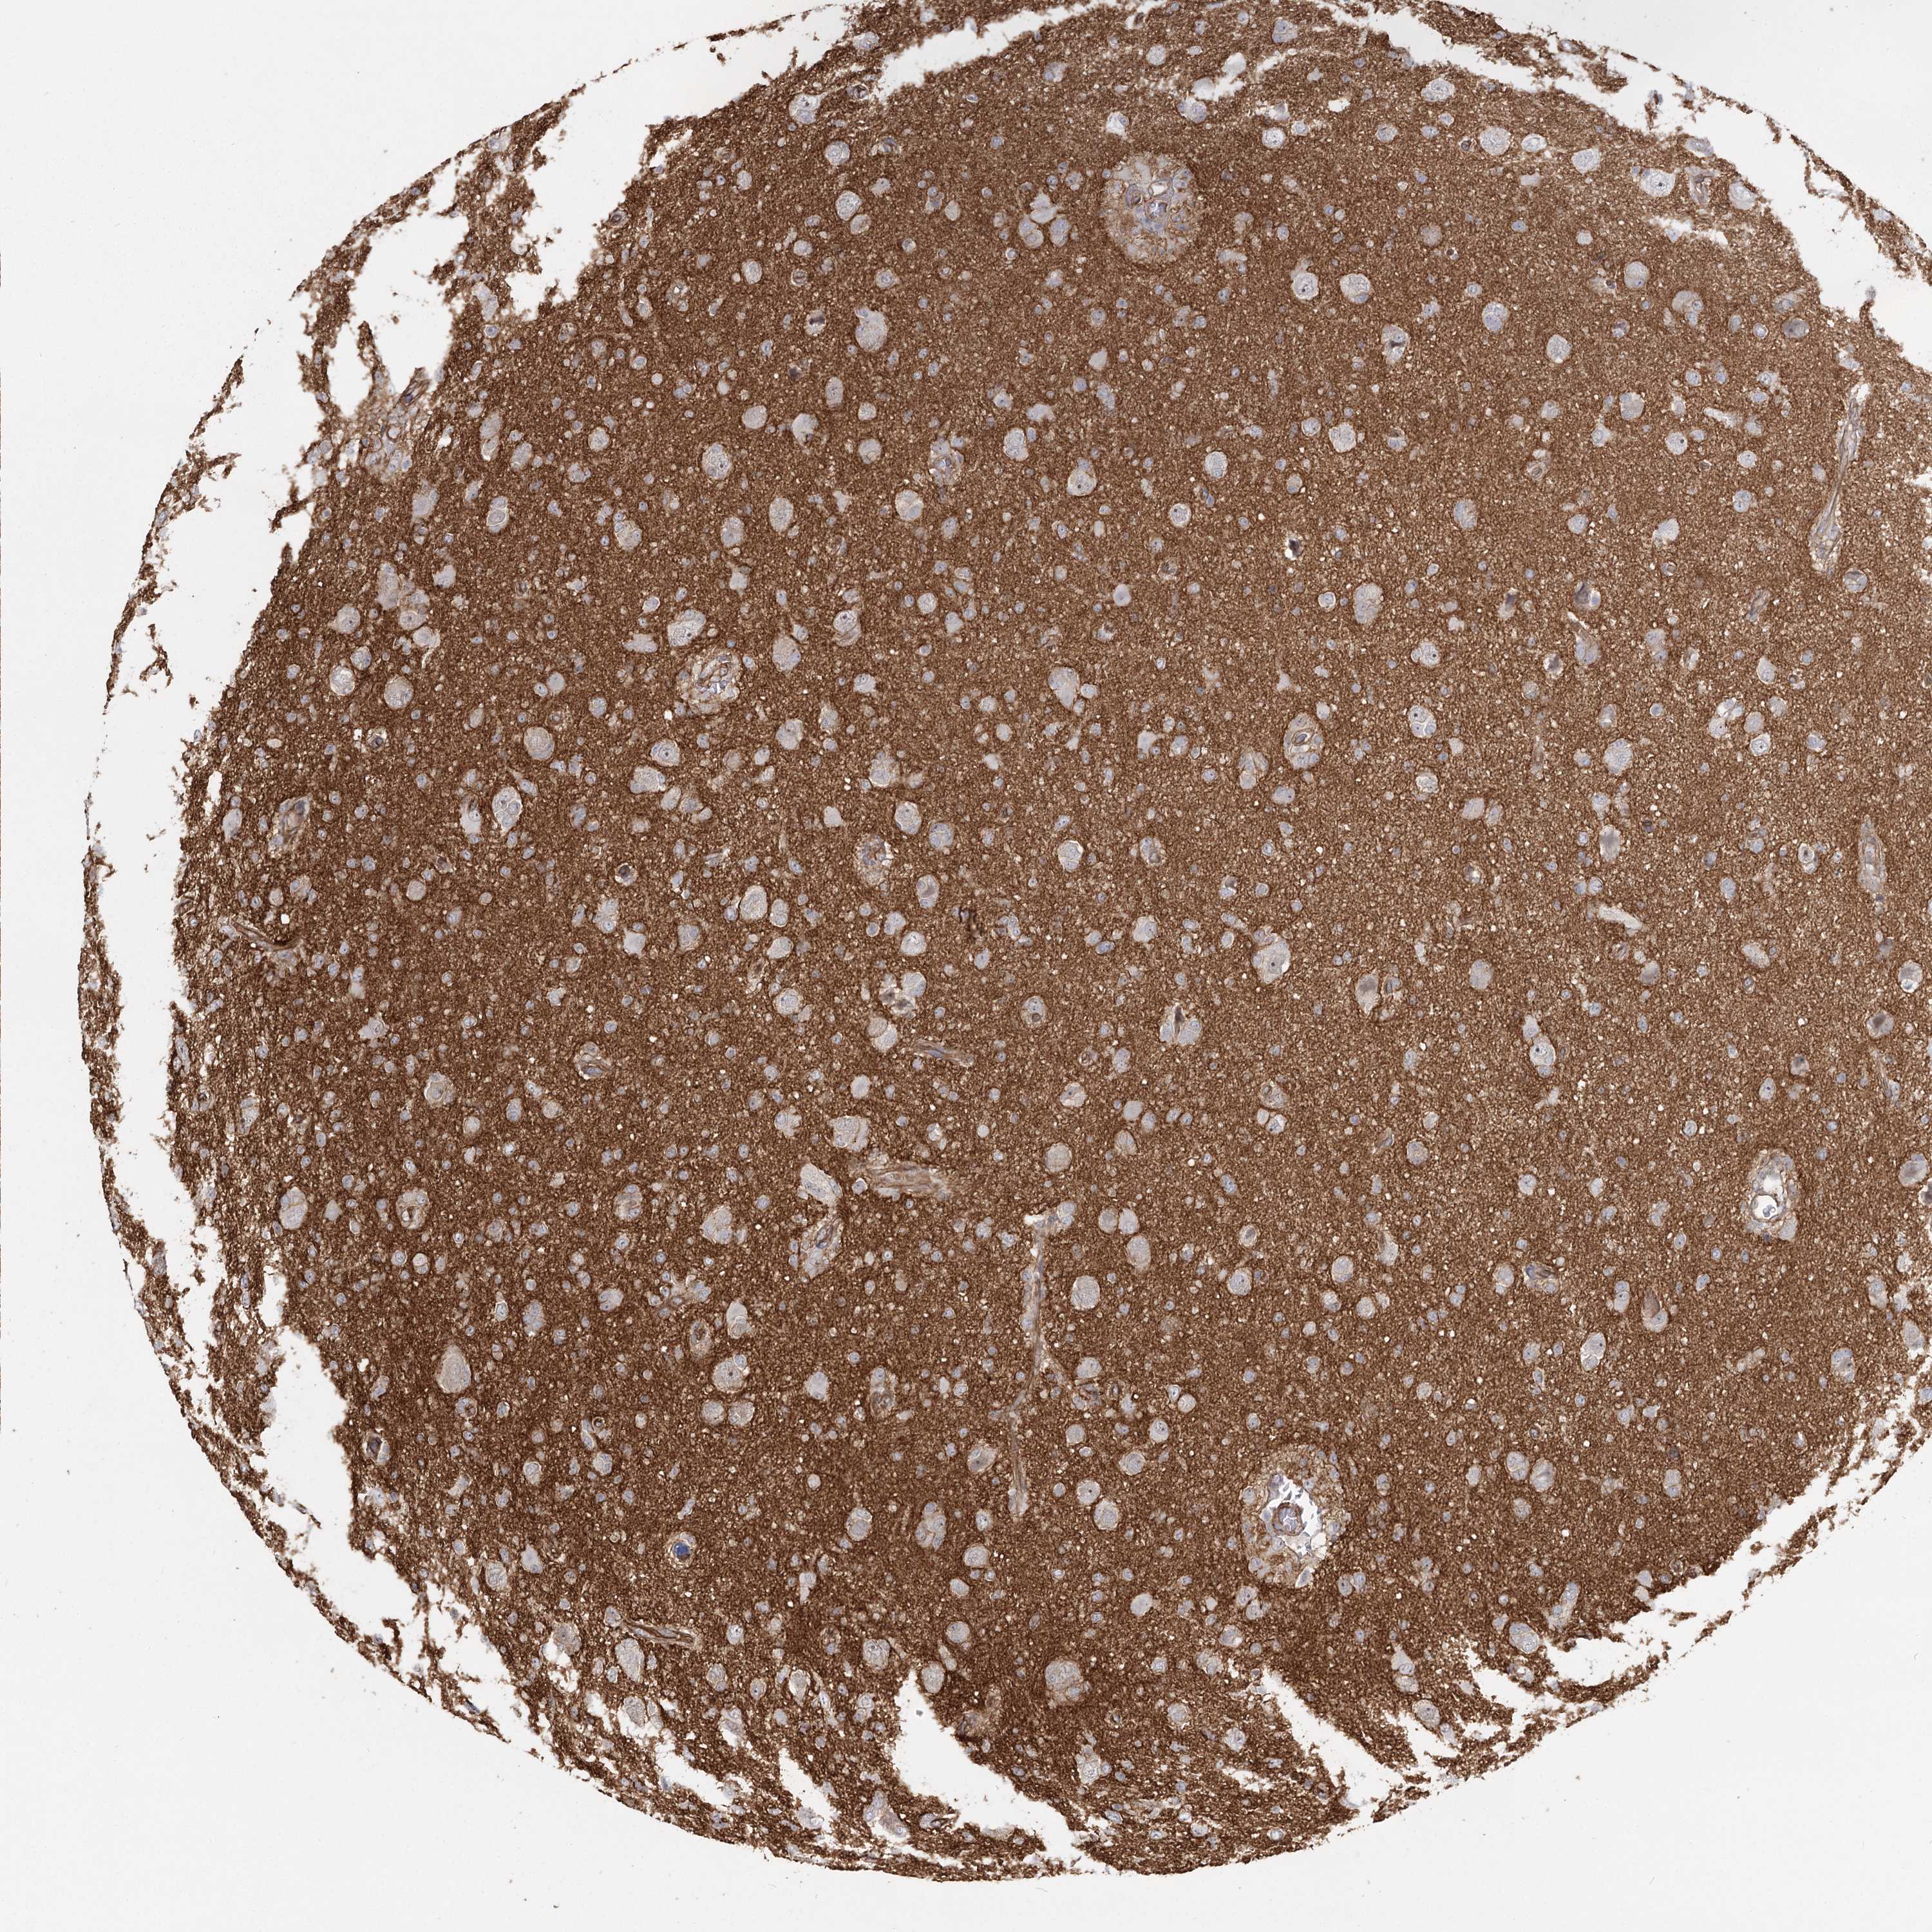

GLIOMA - Protein expressioni

A mouse-over function shows sample information and annotation data. Click on an image to view it in a full screen mode. Samples can be filtered based on level of antibody staining by selecting one or several of the following categories: high, medium, low and not detected. The assay and annotation is described here.

Note that samples used for immunohistochemistry by the Human Protein Atlas do not correspond to samples in the TCGA dataset.

Antibody stainingi

Antibody staining in the annotated cell types in the current human tissue is reported as not detected, low, medium, or high, based on conventional immunohistochemistry profiling in selected tissues. This score is based on the combination of the staining intensity and fraction of stained cells.

Each image is clickable and will lead to virtual microscopy that enables deeper exploration of all samples and also displays staining intensity scores, fraction scores and subcellular localization as well as patient and tissue information for each sample.

Antibody HPA036194

Staining

High

Medium

Low

Not detected

Intensity

Strong

Moderate

Weak

Negative

Quantity

>75%

75%-25%

<25%

None

Location

Nuclear

Cytoplasmic/membranous

Cytoplasmic/membranous,nuclear

Glioma, malignant, Low grade

Glioma, malignant, High grade

Glioblastoma, NOS